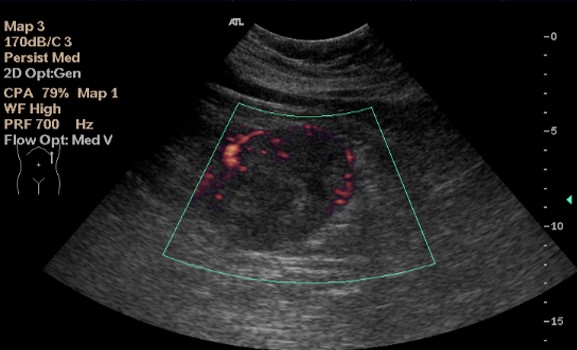

Tumores Renales:

En ecografía la mayoría de los tumores son sólidos.

Ecograficamente pueden ser hipoecogénicos, isoecogénicos, o hiperecogéncios y de gran variedad de formas.

El Doppler presenta una alta sensibilidad para detectar vascularización tumoral.

Doppler